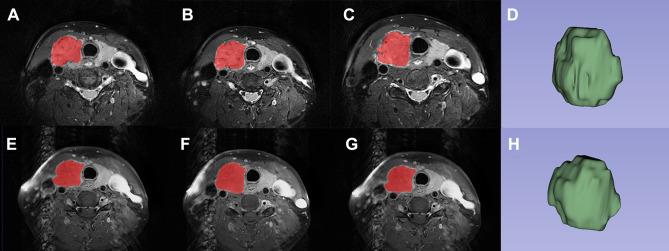

Retrospective analysis was performed on patients with postoperative pathology confirmed papillary thyroid carcinoma (PTC) from 2017 to 2021. One thousand one hundred and thirty-two texture features were extracted from T2-weighted imaging (T2WI) and contrast-enhanced T1-weighted imaging (CE-T1WI) separately by outlining the tumor volume of interest (VOI). Univariate, minimum redundancy maximum relevance (mRMR), and multivariate analyses were used for feature selection to construct 3 models (T2WI, CE-T1WI, and combined model) to predict mutation. The reproducibility between observers was evaluated by intraclass correlation coefficient (ICC). Receiver operating characteristic (ROC) analysis was used to assess the performance of models. The diagnostic performance of the optimal cut-off value of models were calculated and validated by 10-fold cross-validation.

对2017年至2021年术后病理确诊为甲状腺乳头状癌(PTC)的患者进行回顾性分析。通过勾勒感兴趣的肿瘤体积(VOI),分别从T2加权成像(T2WI)和对比增强T1加权成像(CE-T1WI)中提取1132个纹理特征。采用单变量、最小冗余最大相关性(mRMR)和多变量分析进行特征选择,构建3个模型(T2WI、CE-T1WI和联合模型)来预测突变。通过组内相关系数(ICC)评估观察者之间的可重复性。采用受试者操作特征(ROC)分析评估模型的性能。通过10倍交叉验证计算并验证模型最佳截断值的诊断性能。